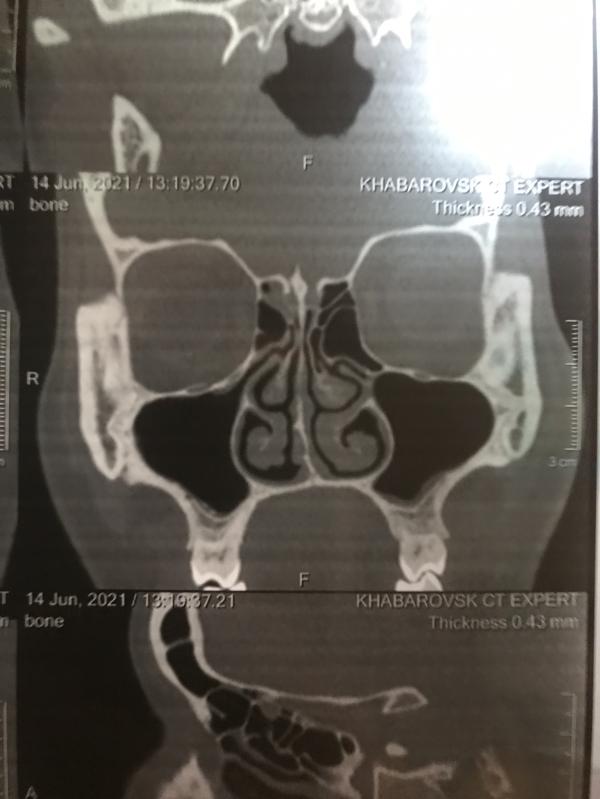

Примерно 17 лет назад (мне было лет 10) я сломала нос. Так и жила с таким носом до сегодняшних дней. Последние лет пять мой сломанный нос доставляем мне дискомфорт, самое ужасное что я им плохо дышу. И вот я решила сходить к ЛОРу. Далее на рентген и СКТ. И везде в заключениях пишут что не значительное искривление. Но визуально это видно, я чувствую что хрящ подвижный, сама кость стала болеть, если непогода то ноет переносица. И самое главное я не могу нормально им дышать… Завтра у меня приём у ЛОРа, и теперь переживаю что мне могут отказать в операции из-за того что в заключениях пишут «..незначительно искривлена»